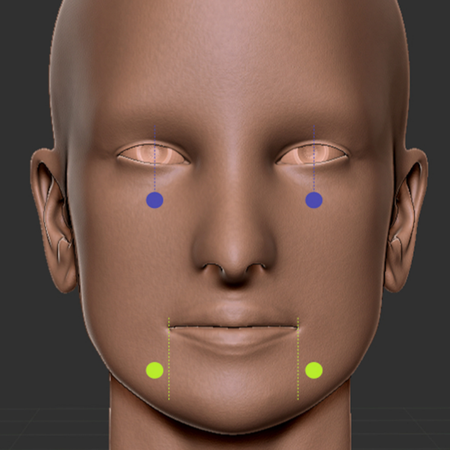

Objetivo: Este trabalho teve como objetivo comparar um novo método de oclusão digital automática, para planejamento cirúrgico virtual em cirurgia ortognática, com um método de oclusão digital e outro método manual convencional. Metodologia: Foi realizado um estudo de validação, com uma amostra de conveniência composta por 20 pacientes, sendo 7 do sexo masculino (35%) e 13 do sexo feminino (65%). Dois avaliadores, de forma independente, determinaram a oclusão final de cada...

Objective: This study aims to compare a new automatic digital occlusion method, for virtual surgical planning in orthognathic surgery, with a conventional digital method and a manual occlusion method. Methodology: A validation study was carried out, with a convenience sample consisting of 20 patients, 7 males (35%) and 13 females (65%). Two evaluators independently determined the final occlusion of each patient, using a conventional manual method, a digital method and an automatic digital...